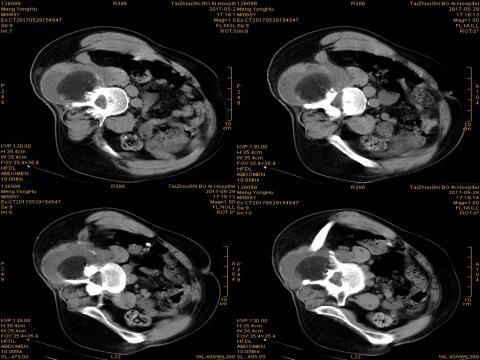

术前准备就绪后,专家团队经过CT扫描定位、穿刺、进针、消融、即刻再次扫描等过程,通过反复冷冻循环后复温,清晰可见患者腰部肿瘤组织逐渐消融。为了尽可能减少患者术中正常脑组织的损伤、降低脑功能的影响,患者全程处于无痛的清醒状态,并能与医生交流,手术非常顺利。

冷冻后即刻评估疗效:冰球(脂肪密度)